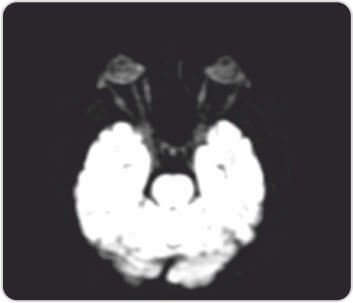

The patient was started on pulse therapy of methyl prednisolone for five days followed by cyclophosphamide and steroids for six cycles. However, despite this, the patient’s condition progressively worsened with increasing breathlessness, severe debilitating joint pains, headache and generalised weakness. Patient also developed sudden loss of vision due to retrobulbar optic neuritis which was treated by IV methyl prednisolone.

Right optic nerve showsincrease in a signal due to optic neuritis